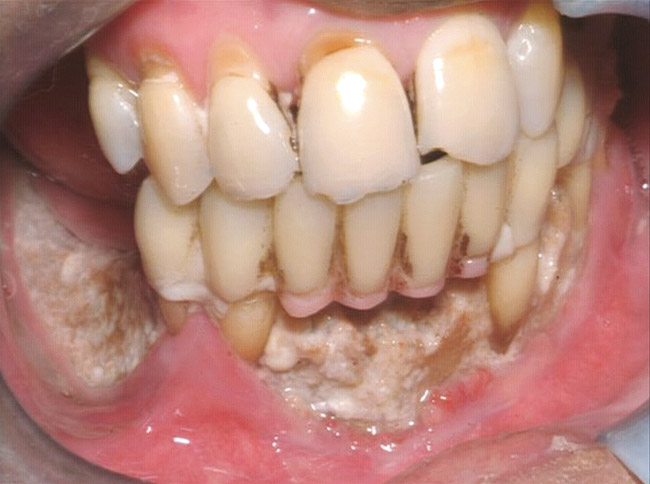

Under the sextant approach, one quadrant is treated and the patient is left to heal for 2 months before proceeding to any additional quadrants. While the patient heals, a 10-day course of antibiotics and 2 months of twice-daily chlorhexidine rinsing may be prescribed. Figure 4 shows a patient who was taking oral bisphosphonates for 3 years and was treated with the sextant approach. As seen in the radiograph, the patient has one molar in the lower right quadrant. This tooth was extracted and the patient was given 2 months to heal (Figure 5 and Figure 6). The patient was placed on antibiotics and chlorhexidine rinse. After 2 months, no signs of BRONJ were observed, and the anterior teeth were scheduled for extraction. They were extracted as atraumatically as possible, and the site was sutured (Figure 7 and Figure 8). The patient then was given another 2 months to heal, following the previous protocol. After 2 months of healing, no BRONJ was observed (Figure 9). The patient was able to move forward with the prosthesis.

Figure 5  After 2 months of healing, the lower right quadrant showed no signs of BRONJ and the anterior teeth were scheduled for extraction.

Figure 5

Figure 6  After 2 months of healing, the lower right quadrant showed no signs of BRONJ and the anterior teeth were scheduled for extraction.

Figure 6

Figure 7  Anterior extraction sites after atraumatic removal.

Figure 7

Figure 8  Anterior extraction sites after atraumatic removal.

Figure 8

Figure 9  Anterior extraction sites after atraumatic removal.